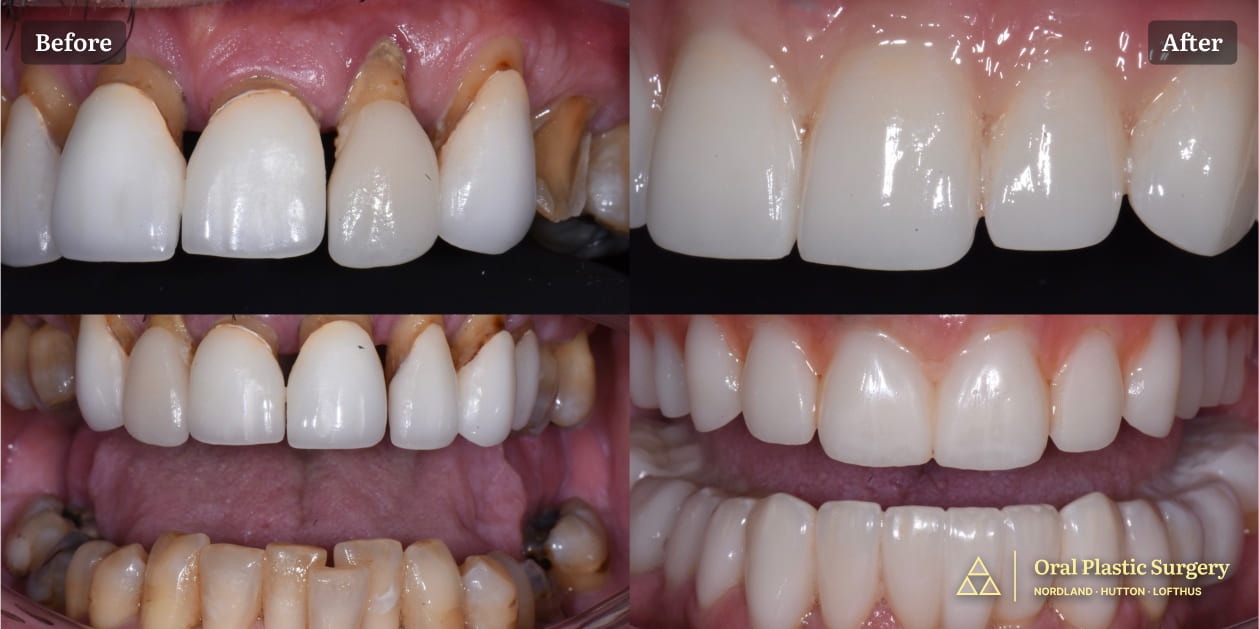

A full smile transformation- loose, painful teeth were removed and replaced with a stable, implant-supported restoration

A full smile transformation: loose, painful teeth were removed and replaced with a stable, implant-supported restoration.

Restoring Health, Comfort, and Aesthetics by Eliminating Diseased Teeth Before After 4 Pictures